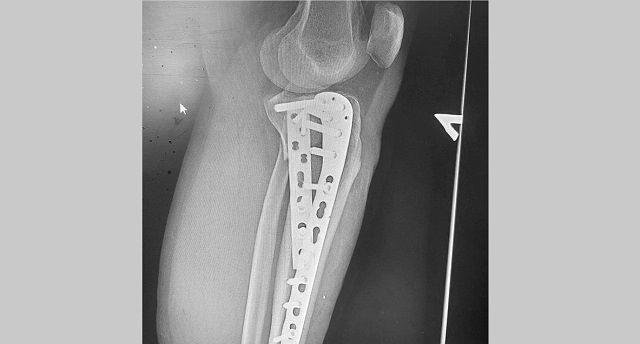

В Казани врачи горбольницы №7 прооперировали мужчину, который в результате падения с самоката получил многооскольчатый перелом верхнего суставного конца большеберцовой кости с разрывом боковых связок.

В ходе операции медики выполнили остеосинтез пластинами и винтами, а также восстановили связки коленного сустава. По словам медиков, самокат в последнее время стал популярным средством попадания в травматологическое отделение.